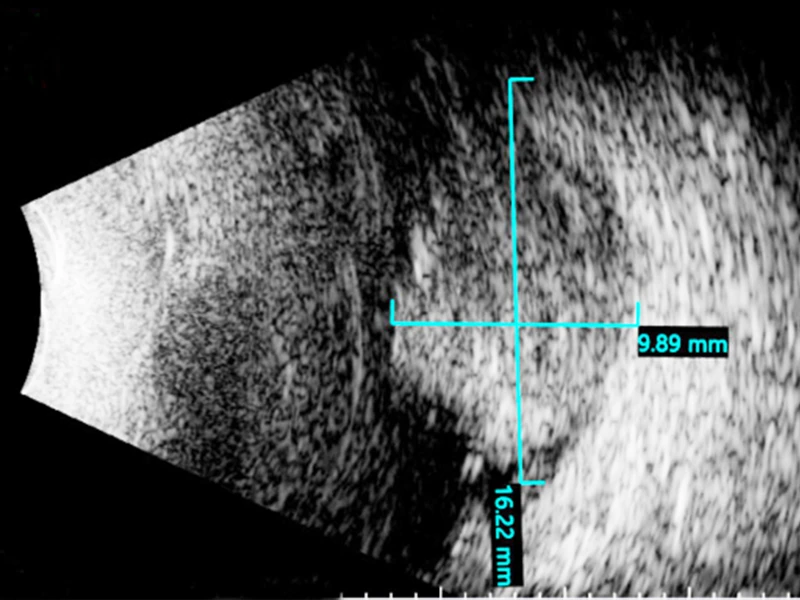

The success of the first young patient is cause for encouragement. Dr. Semenova, who led the multidisciplinary team, discovered the tumor (nearly 10 millimeters in thickness) arising in his retina, and recommended a two-part course of treatment. It consisted of intra-arterial chemotherapy done by Johanna Fifi, MD, a neuroendovascular surgeon and Professor of Neurosurgery, Neurology, and Radiology at Icahn Mount Sinai, to target the tumor, followed by a series of intravitreal chemotherapy injections by Dr. Semenova to eliminate the tumor seeds floating in the vitreous.

Ultrasound of the retinal tumor measuring 9.9 x 16.2 mm in size before the treatment.